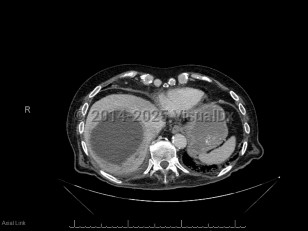

Pyogenic liver abscess

A pyogenic liver abscess is a collection of pus in the liver as the result of bacterial (or rarely fungal) infection.

The two most common routes that pathogens use to invade the liver and cause an abscess are through the biliary tree (if the biliary tree is obstructed, then cholangitis may follow, which can be complicated by hepatic abscess formation) and through the portal venous system (the portal venous system provides drainage of intraabdominal organs, and pathogens causing diverticulitis or appendicitis, for example, will drain through the portal venous system and may form hepatic abscesses). Liver abscesses may also form due to hematogenous seeding of the liver in the setting of bacteremia. Other intraabdominal abscesses may enlarge and involve the liver by contiguous spread. Rarely, pathogens may seed the liver in the setting of anatomic abnormalities (eg, in the setting of a liver hematoma) or due to direct inoculation in the setting of trauma. In 20%-40% of cases, no obvious cause for the liver abscess is identified.